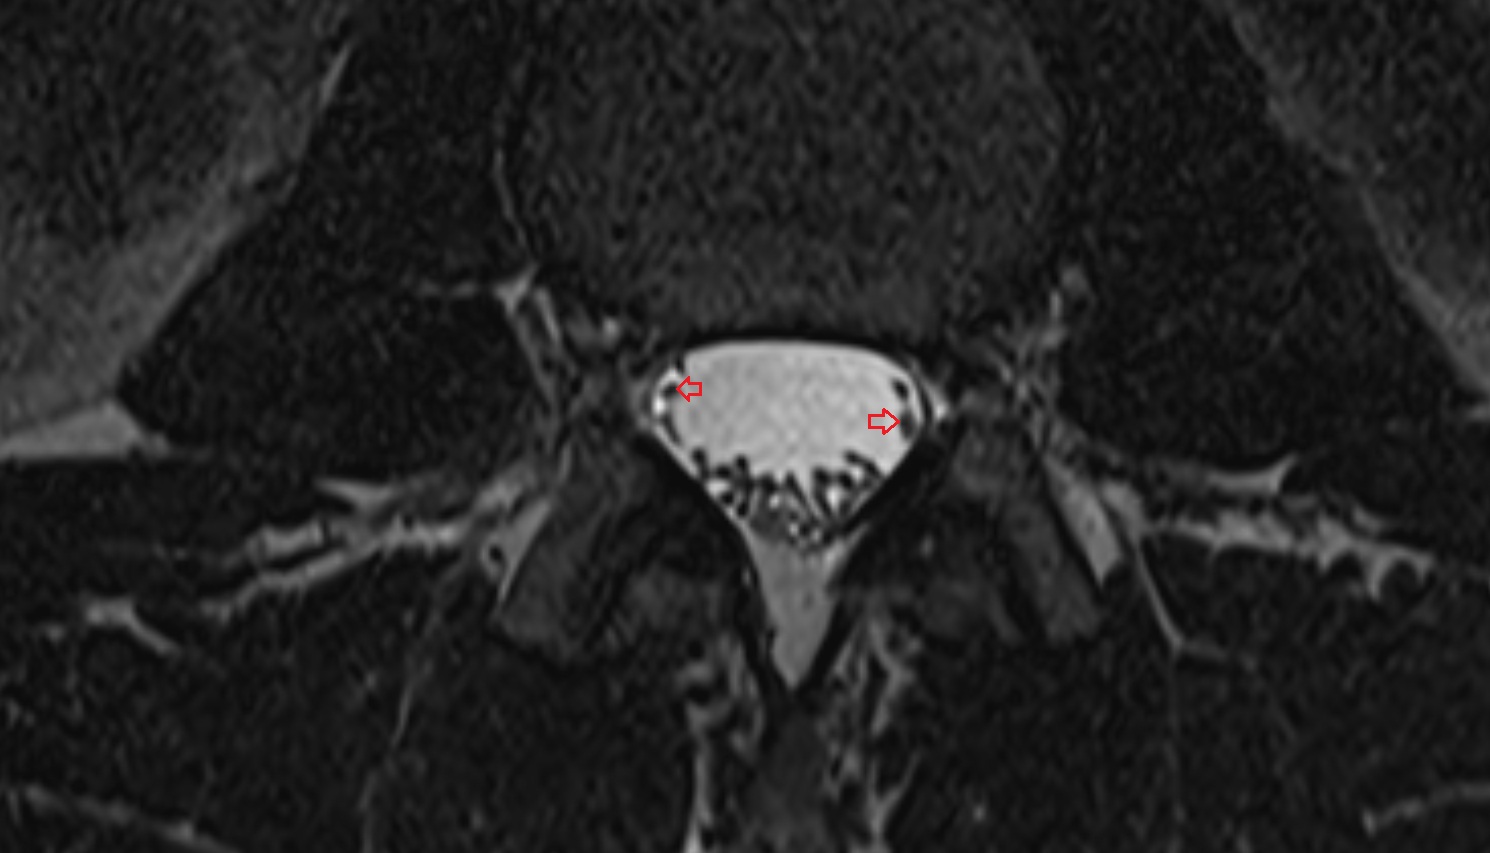

- Traversing nerve root of spinal nerve

- Exiting nerve root of spinal nerve

- Dorsal traversing nerve root

- Ventral traversing nerve root

- Dorsal exiting nerve root

- Ventral exiting nerve root

- Dorsal root ganglion of spinal nerve